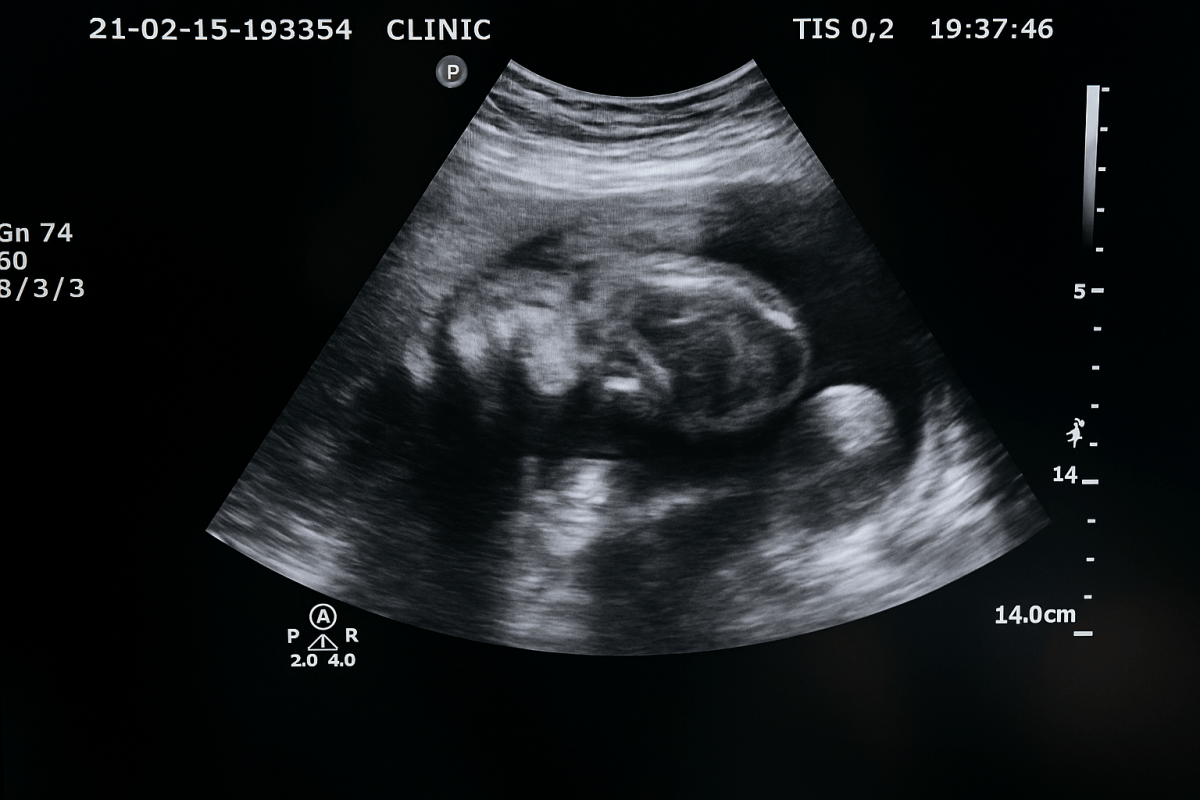

Ultrasound: Visual Confirmation Later in Pregnancy

• Window: Most reliable at the 18–22 week anatomy scan when a clear view is possible.

• What affects it: Fetal position (legs crossed, cord placement) can limit visibility; brief rescan usually resolves it.

• Role: Complements early blood tests with a visual confirmation.

• Best for: Families who prefer to see the anatomy and confirm results during routine care.